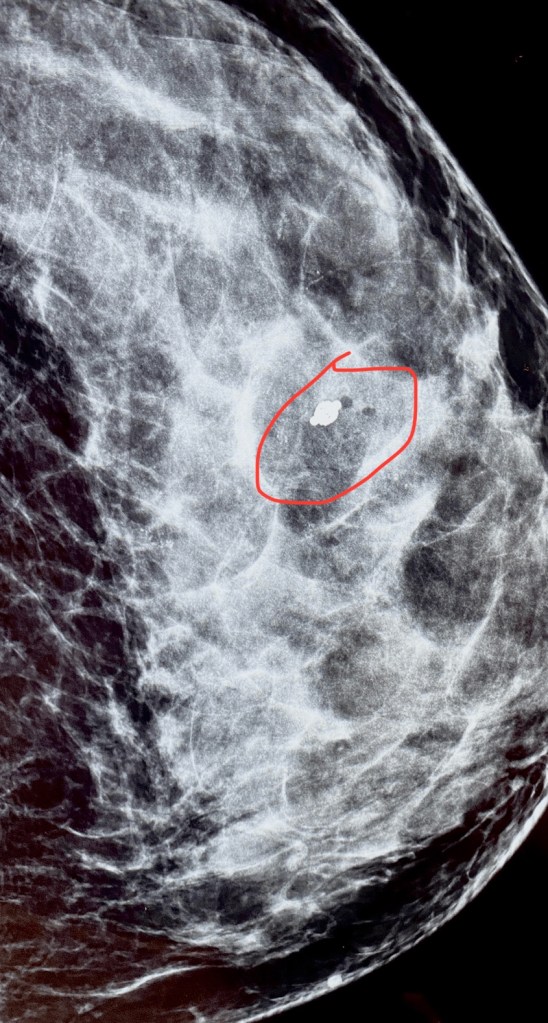

March 16 finally arrived, And Brian and I headed down to Mercy Breast Care, hoping to get some answers. Brian had to wait in the car because of the COVID-19 restrictions, and the especially considering the potential vulnerability of the patients that are seen in a breast radiology clinic. When I checked in with the receptionist, I asked the receptionist to verify which doctor I would be seeing…Because of my prior visit there I was hoping it would be Dr. Adnan Qalbani as he was such a comforting and compassionate provider during my past experience with the clinic. I was shocked when she said it would be neither Qalbani (Adnan’s mother is also a breast radiologist)…The senior Qalbani was not working in the clinic (especially since the pandemic began) and Adnan was out of town. She informed me I would be seeing Dr. Jill Veccio, his associate from Denver. So right off the bat, I was a little bit apprehensive with a new face in the mix, but those fears soon vanished as soon as I met her. First stop was the dressing room – to change into my “open in the front” hospital robe , and shortly after I changed, the tech came to get me for my ultrasound. As you can imagine I was nervously chatting with her and just kind of wondering what my reality was going to end up looking like… Of course every time she had measure some thing and click the mouse, I’d like “what was that”? …I remember seeing her put some numbers and measurements on the screen… And she left to get Dr.Jill….After what seemed like a really long time, They came into the room Dr.Jill instantly commented that she liked my cowboy boots…😂 she knew the way to this girl’s “good side”. She then explained that on my screening mammogram, they had seen a lot of calcifications and she was hoping to see that they laid out into a nice pattern instead of “random calcifications” here and there. She couldn’t seem to find any sort of pattern or uniformity in the layout of the calcifications despite having me change my position a few times. If there is a pattern or some sort of uniform appearance to the calcifications, they are more likely to be associated with a benign process (in other words not cancerous). Still, she did not raise the alarms yet…she told me that “sometimes gravity can help, so when we have you on the stereotactic table…” (which is basically what I would describe as a “dangling mammogram”) she continued “and once you’re in that position and sometimes those calcifications will fall into a pattern”. Dr. Jill went to consult with another patient…I went to the next waiting room 😂…The tech was a sweetheart (&also named Jill) & such a joy to visit with. They really know what they’re doing at that place and how to set the patient at ease that’s for sure… So I got up on the stereotactic table… It was quite high up and I love a challenge so I was like nope I got this and I crawled up there without batting an eye…It was basically like an unpadded massage table (very firm and not comfortable… I think I was dehydrated at the time I just couldn’t seem to get comfortable)but once we figured it out, she got my left boob adequately “dropped” through the hole ,got it all compressed & voila! the image of my left breast was up on the monitor. I do remember her looking for the right area and gasping “but you have so many!”…I believe I said “Whelp …I’m an all or nothing type of girl…anything I do , I go big or go home!” We both kind of laughed and Dr.Jill came back in, made sure everything was where it needed to be on the screen , Thshe said unfortunately those are not laying out like I hoped they would, so we’re going to have to proceed with the biopsy. She gave me a lidocaine shot to numb the biopsy area on my outer lower quadrant of my left breast. She was so comforting and did such a great job explaining every little movement she was making, as well as preparing me for what sounds I would be hearing (i.e,” now you’re going to hear a popping noise…like opening a bottle of champagne and that’s just a needle going in”and then she explained I was hearing the biopsy samples being vacuumed back up into the collection port, and then after the news collects three tissue samples, the machine washes out (also called lavage or irrigation) the inside of my breast where the needle was with normal saline…And then they placed a marker “so the surgeon could find it if I needed surgery” …that’s probably when I started to think…uhhhh this is probably not going to end the way that I hoped…I just felt like everything was gonna be fine and really be some diabetes related change that they were seeing in my breast or some other benign process. The tech applied pressure to the biopsy site incision for several minutes and then took a another mammogram image so we could see that the marker was in the right spot etc. I was able to sneak a picture -before I knew it wasn’t allowed…I just had my phone out because I was texting Brian that I was about done and quick snapped a picture of the screen. I still think it’s weird that you’re not allowed to take your own pictures like that but I guess I can see where sometimes information like that could be dangerous in the wrong hands. The tech gave me a little round ice pack to put inside of my bra and I was on my merry way! Now I just had to wait for the doctor to call me with my results in 3 to 4 daysI… was hoping that I would get the results by Friday as this was a Tuesday and I wouldn’t have to go all weekend waiting and wondering. Honestly, I was just ready to get my “good news” and move on. I think that was just me being in denial, because there were several intuitive moments and signs, in retrospect, an apparent attempt to prepare me for what was coming, but like they say, ignorance is bliss!